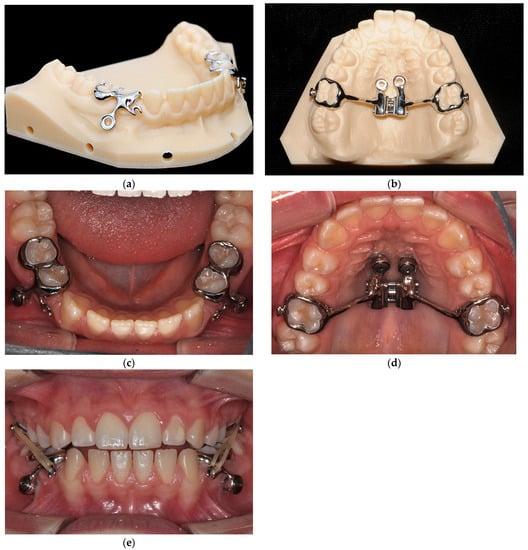

Concept for the Treatment of Class III Anomalies with a Skeletally Anchored Appliance Fabricated in the CAD/CAM Process—The MIRA Appliance

3.3. Treatment Progress